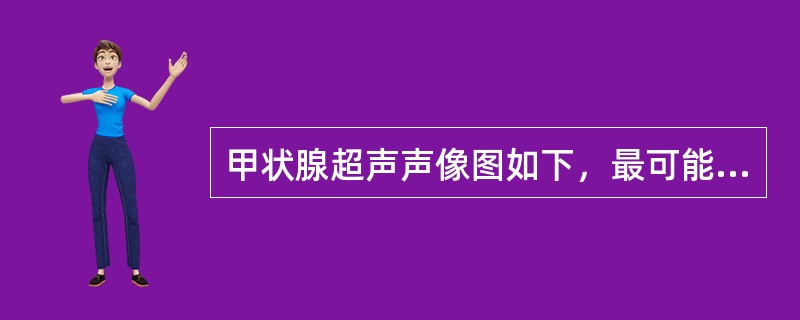

甲状腺超声声像图如下,最可能的诊断为()。

A . 甲状腺囊肿

B . 结节性甲状腺肿并囊变

C . 甲状腺腺瘤并囊变

D . 甲状腺囊腺癌

E . 甲状腺炎

甲状腺超声声像图如下,最可能的诊断为()

[单选题]甲状腺超声声像图如下,最可能的诊断为()A . 甲状腺囊肿B . 结节性甲状腺肿并囊变C . 甲状腺腺瘤并囊变D . 甲状腺囊腺癌E . 甲状腺炎

甲状腺超声声像图如下,最可能的诊断为()

[单选题]甲状腺超声声像图如下,最可能的诊断为()A .甲状腺囊肿B .结节性甲状腺肿并囊变C .甲状腺腺瘤并囊变D .甲状腺囊腺癌E .甲状腺炎